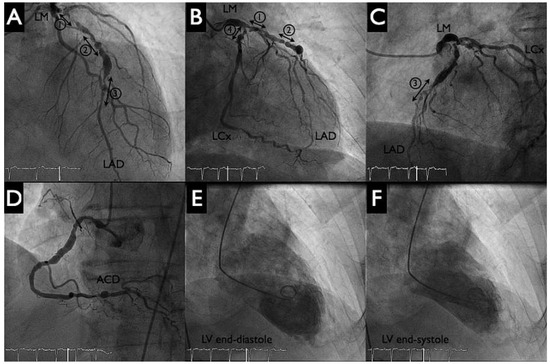

HeartMate PHP Axial Pump for High-Risk PCI

by Diego Arroyo, Serban Puricel, Mario Togni and Stéphane Cook

Cardiovasc. Med. 2016, 19(9), 241; https://doi.org/10.4414/cvm.2016.00430 - 21 Sep 2016

Percutaneous left ventricular assist devices (pVADs) can provide temporary circulatory support during high-risk percutaneous coronary interventions (PCIs). We describe the first case in Switzerland of high-risk PCI with a new pVAD, the HeartMate PHP axial pump (St Jude Medical). Full article